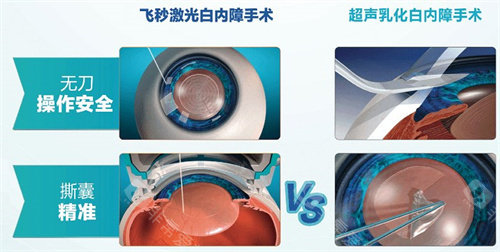

白内障正规开展了多种白内障手术,包括超声乳化白内障吸除术等,手术技术成熟,术后结果良好。

此外,科室还开展了一些潮流的眼科手术技术,如飞秒激光辅助白内障手术等,大大提高了手术的可靠性和有效性。